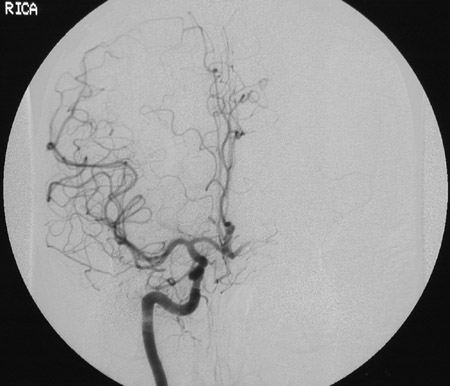

This cerebral angiogram seen coronally after injection of contrast into the right internal carotid artery demonstrates circulation of the anterior cerebral and the middle cerebral arteries. Note the watershed region between these circulations.